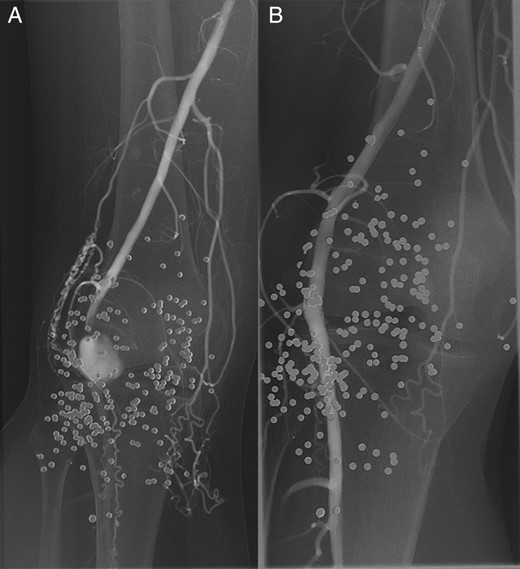

Angiography, via an antegrade right femoral approach, showed a false aneurysm of the popliteal artery at the knee joint level. There was occlusion of the calf vessels. A 6 mm × 25 mm Viabahn (Gore) covered stent was deployed to exclude the pseudoaneurysm, and a thrombolysis catheter was left in situ in the below-knee popliteal artery (Fig. 1). Thrombolysis was started using alteplase at a rate of 1 mg/h, with a concurrent infusion of heparin 400 IU/h via the arterial sheath, as per local protocol.

A digital subtraction angiogram of the right popliteal artery demonstrating the pseudoaneurysm, pre- (A) and post- (B) stenting. Note the numerous pellets in the soft tissues.